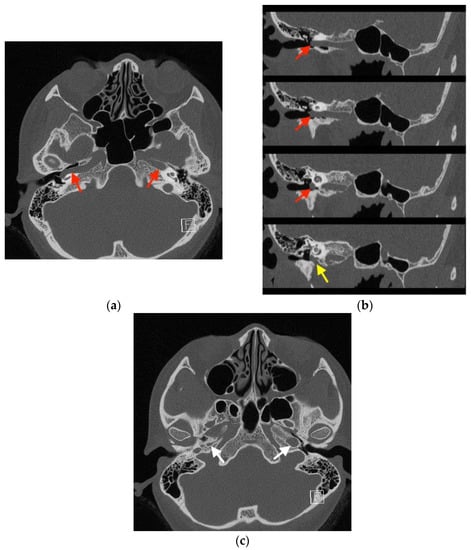

2. Case Report